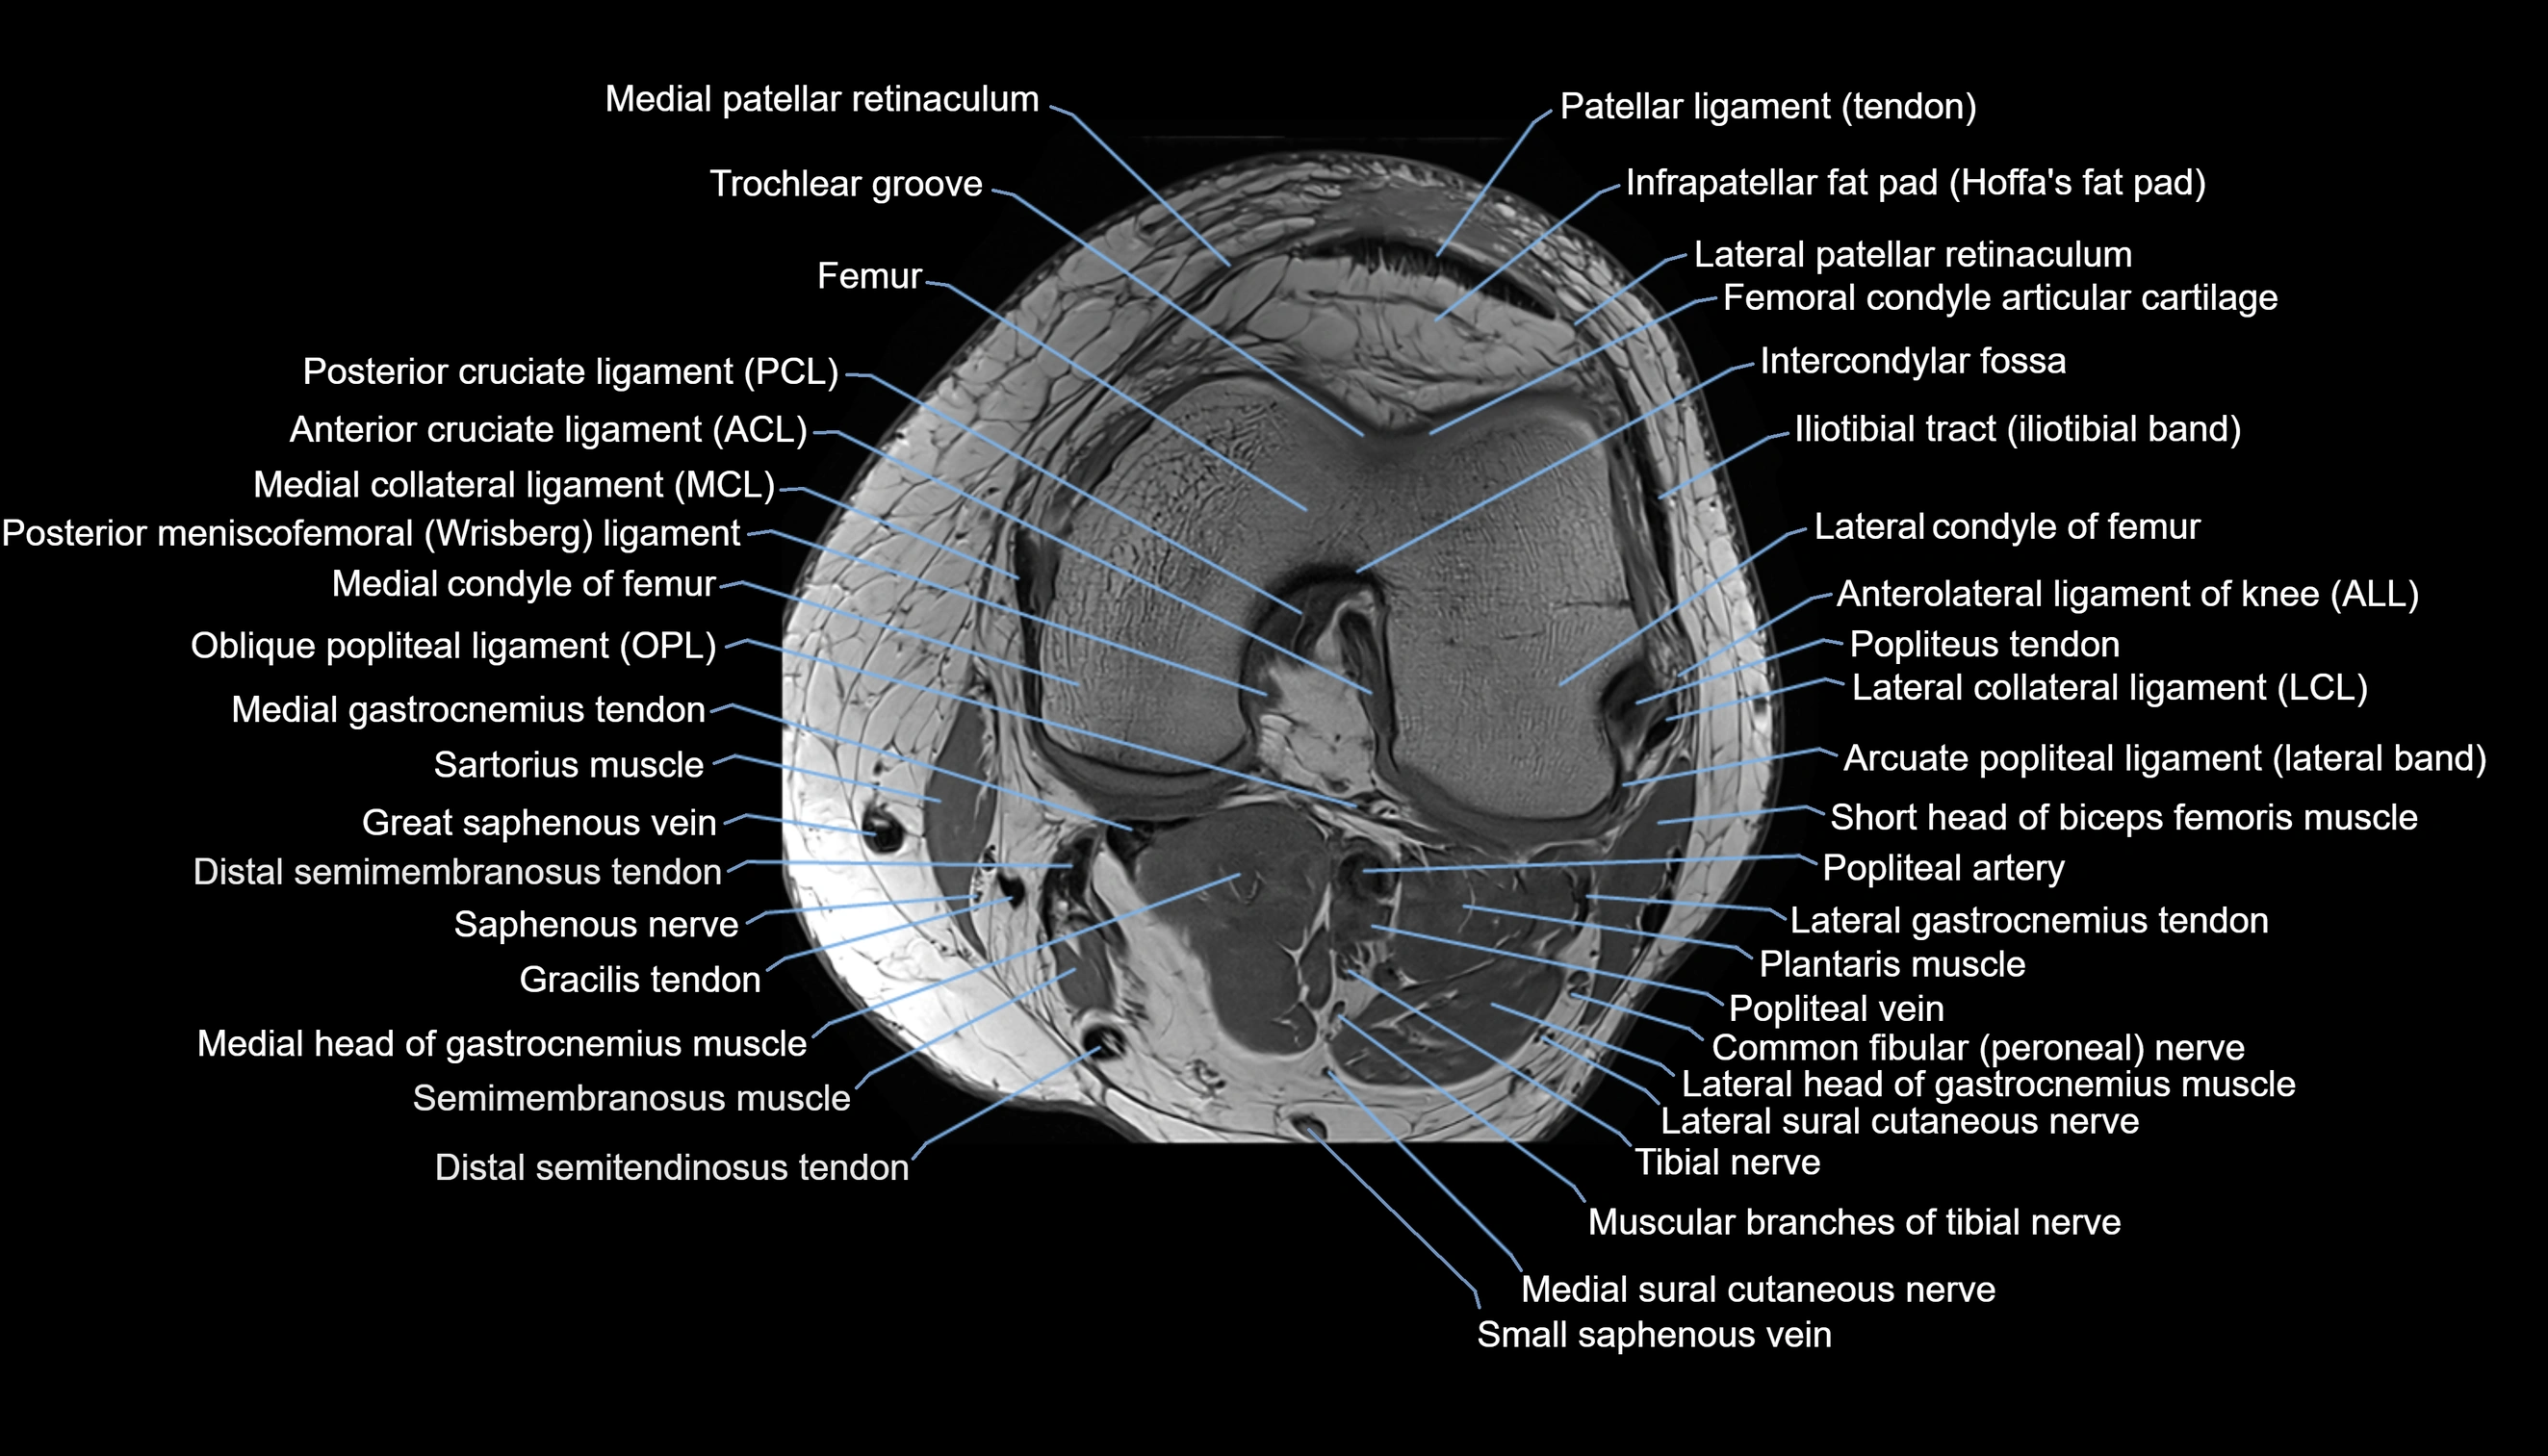

- Anterior cruciate ligament

- Anterolateral ligament of knee

- Arcuate popliteal ligament

- Femoral condyle articular cartilage

- Intercondylar fossa

- Lateral collateral ligament

- Lateral condyle of femur

- Lateral gastrocnemius tendon

- Lateral head of gastrocnemius muscle

- Lateral patellar retinaculum

- Medial collateral ligament

- Medial condyle of femur

- Medial gastrocnemius tendon

- Medial head of gastrocnemius muscle

- Medial patellar retinaculum

- Medial sural cutaneous nerve

- Muscular branches of tibial nerve

- Oblique popliteal ligament

- Popliteal artery

- Popliteal vein

- Popliteus tendon

- Posterior cruciate ligament

- Sartorius muscle

- Semimembranosus muscle

- Small saphenous vein

- Tibial nerve

- Trochlear groove